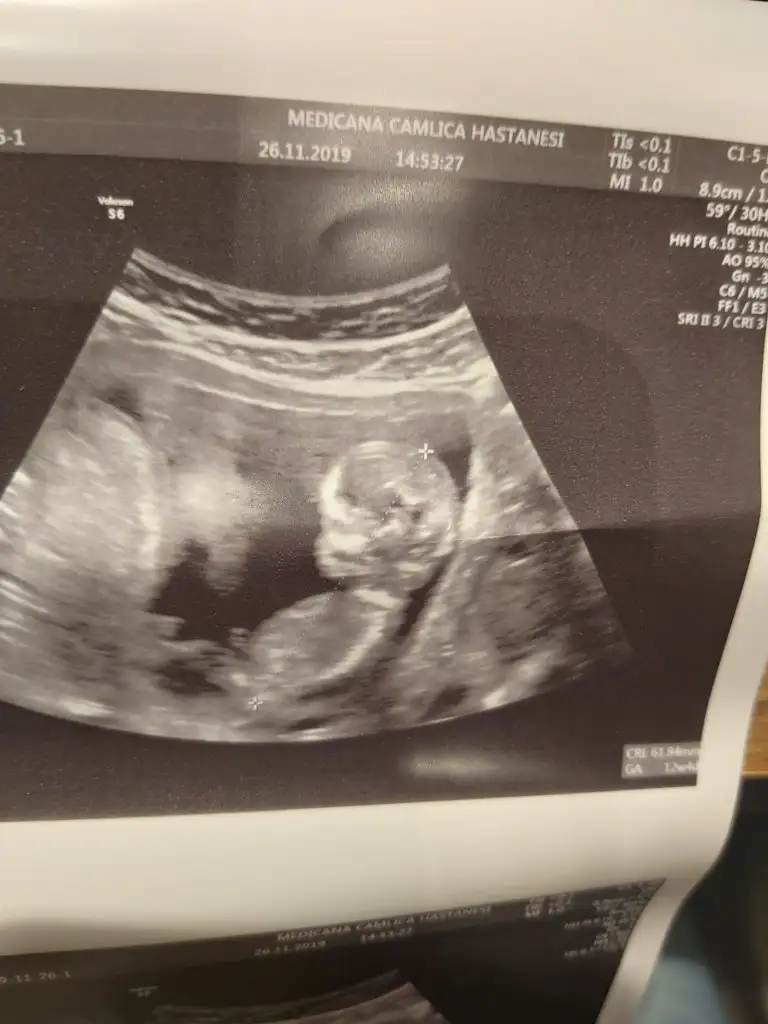

13. Haftalık 11 ve 12. Haftalıkken doktora gitmedik kontrolümüz 13. Haftaya denk geldi o yüzden bu başka da var ama net değil ki atayım ben yine deerkek gibi başka usg var kaç haftalık

erkek gibi başka usg var kaç haftalık

Öğrendiniz mi neymiş ben genelde kıza benzetiyorum nedenseBenim de kız demiştiniz![]()